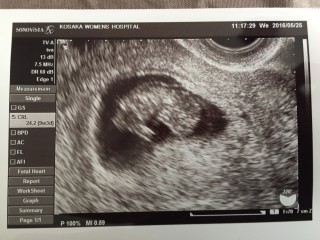

写真:9w3d:とまるみさん

頭殿長22.4ミリ。

妊娠5週〜8週はずっと茶色の出血があり自宅安静の日々を過ごしていたため、ものすごく心配していましたが、順調とのことでホッとしました(*^^*)

小さいけど頭、胴体、手足がはっきり分かりました。

胴体の真ん中の心臓がピコピコ光っているのを見ていると、愛おしさが込み上げました。

1年の不妊治療を経てやっとやっと授かった子なので、本当に嬉しい気持ちでいっぱいになりました。